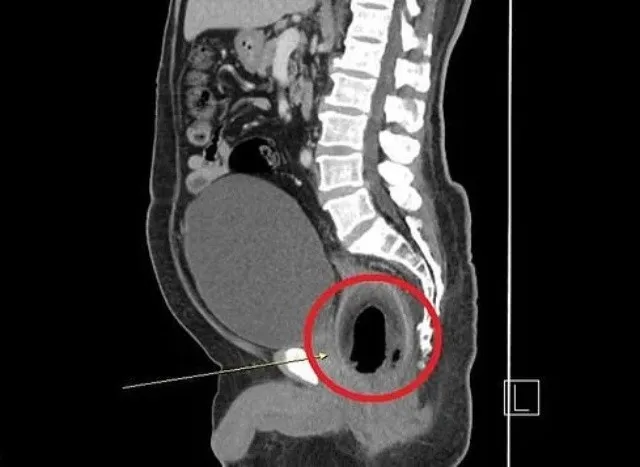

Producto de esta acción, el sujeto no podía orinar, se quejaba de un fuerte dolor abdominal y estaba con estreñimiento. A pesar de estos síntomas, el sujeto no acudió al médico. Tras volverse el dolor insoportable, luego de dos días el hombre llegó hasta el hospital en busca de ayuda.El paciente se sometió a una cirugía de emergencia después de que las pruebas mostraran que se había insertado un coco de nueve centímetros de largo en el recto, según un comunicado del British Journal of Surgery.

El coco de 9 cm de largo fue extraído por laparotomía, una operación que implica la apertura del abdomen. El paciente tuvo suerte de seguir vivo. Afortunadamente, no sufrió daños internos graves. Pero, los médicos le recomendaron que no volviera a hacer esto. El paciente admitió que se puso el coco en el recto para estimularlo. “